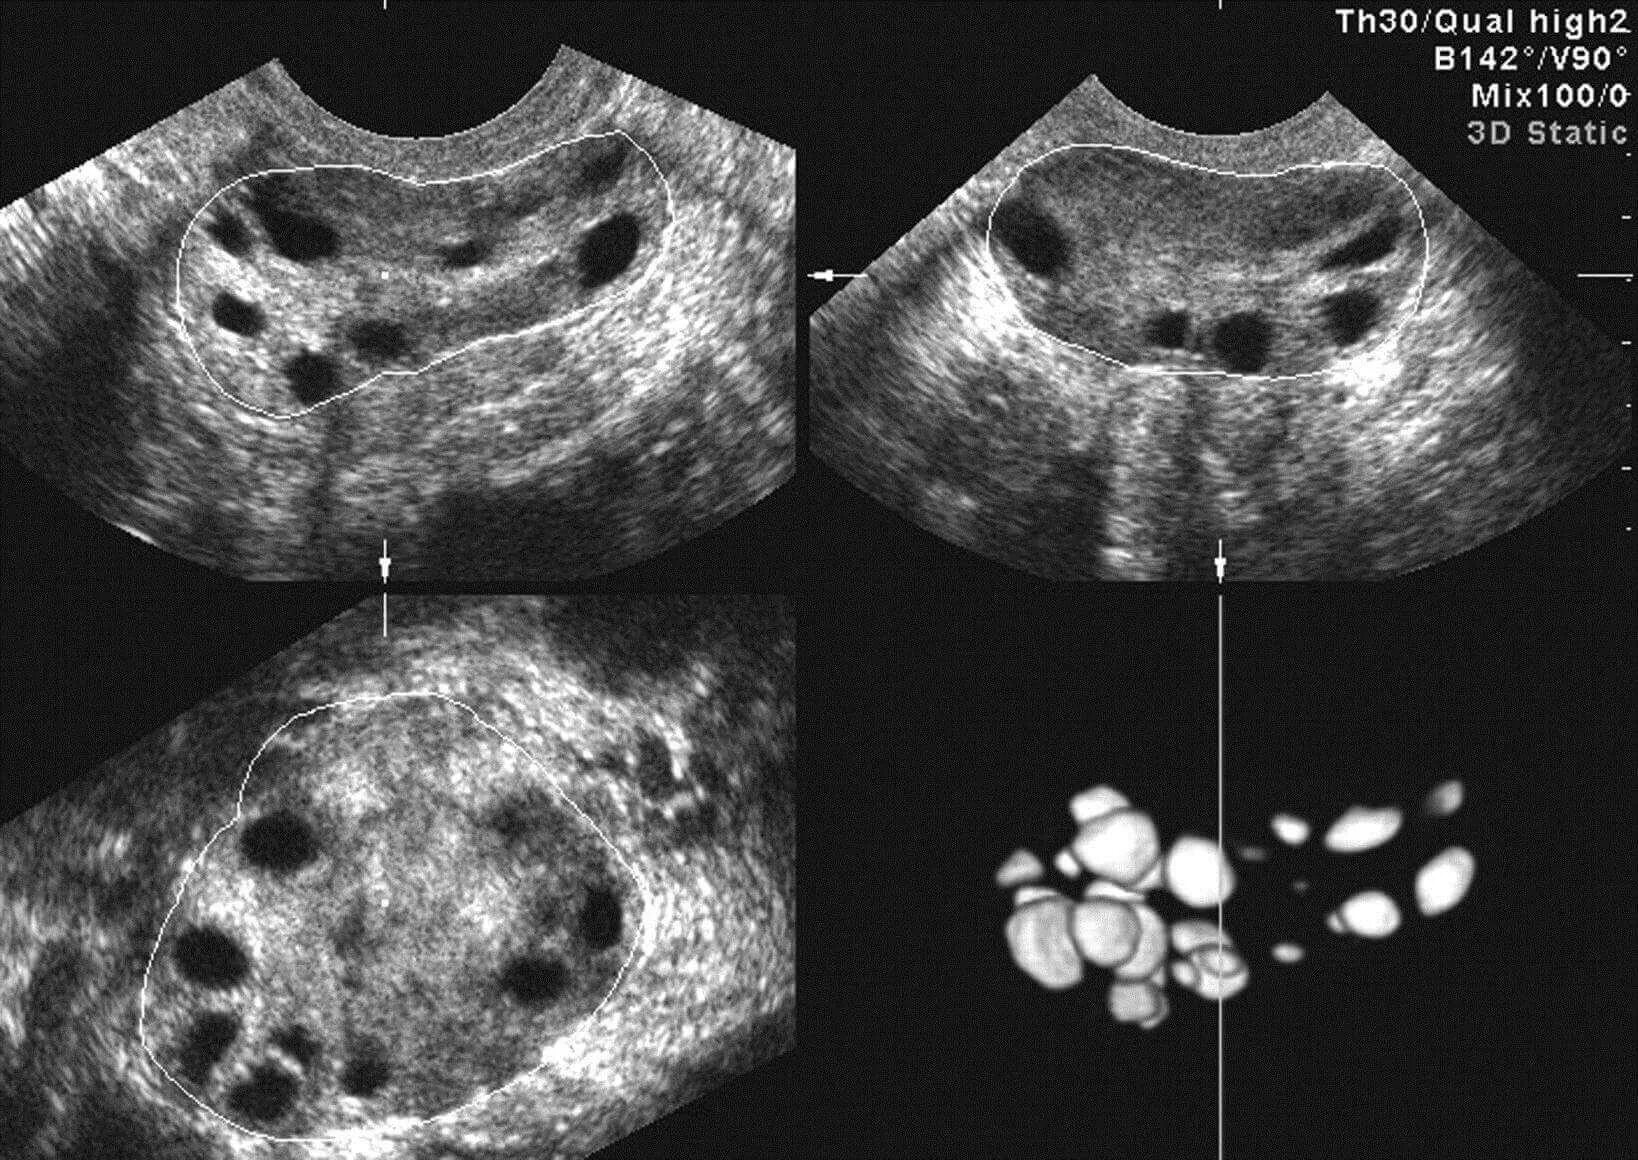

Как выглядит поликистоз яичников